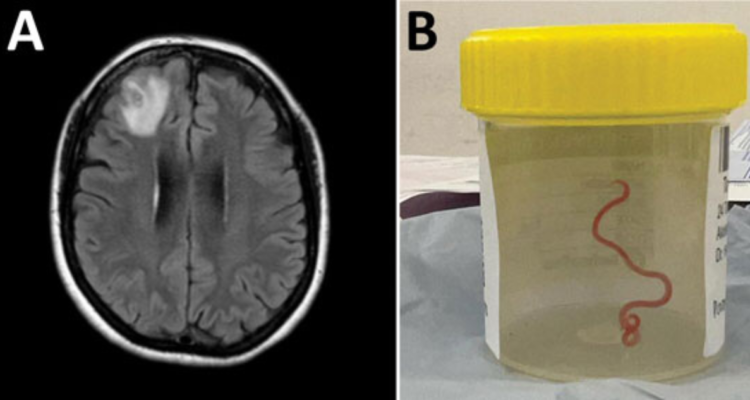

La jornada de este martes se confirmó la noticia de la extracción de una lombriz intestinal viva de ocho centímetros desde el cerebro de una mujer australiana. Este es el primer caso en humanos, según informaron especialistas.

Finalmente, fue un neurocirujano del Hospital de Camberra el que exploró su caso y encontró la lombriz, la que fue extraída viva y retorciéndose del cerebro de la paciente. Hasta el momento no se ha precisado la fecha exacta de la extracción, mientras que la mujer sigue siendo examinada por los especialistas en enfermedades infecciosas y cerebro.